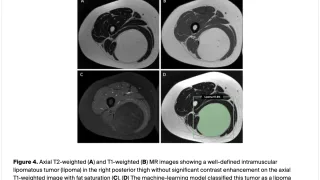

手術日+728日目 2026/2/25(水)(筋肉内神経鞘腫)